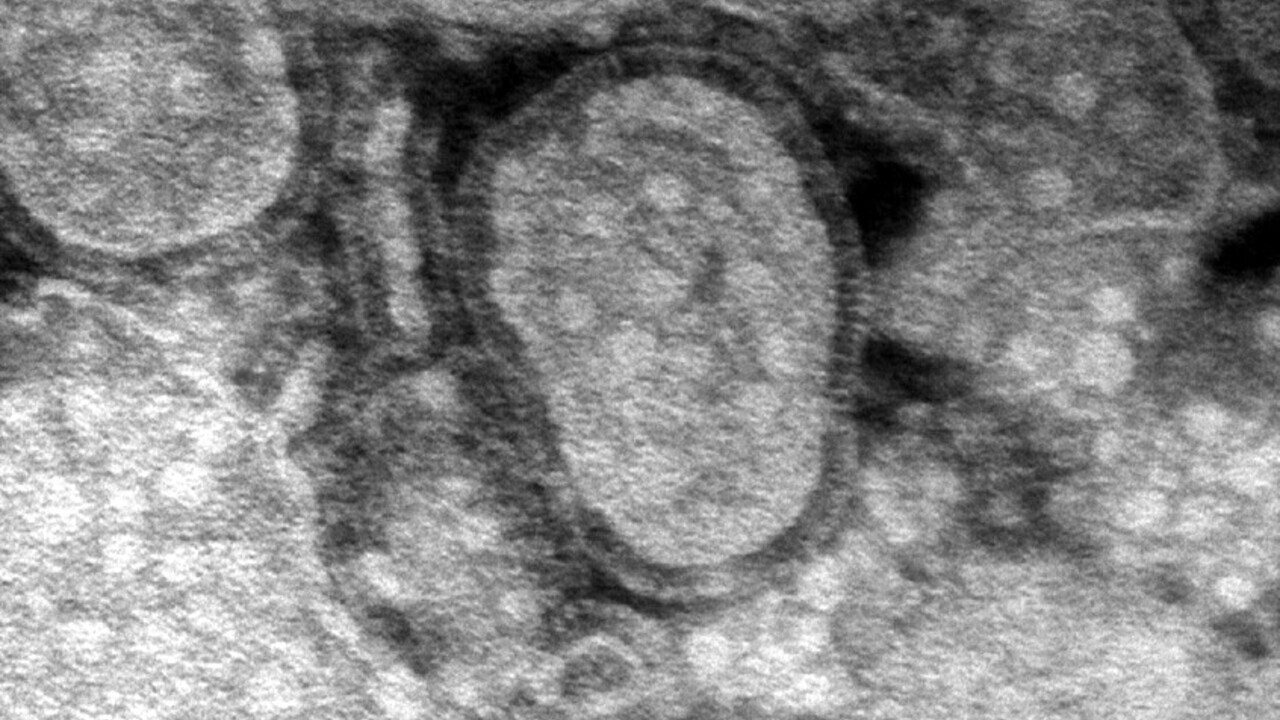

According to the expert, metapneumovirus is actually not as deadly as the coronavirus. He noted that after a pandemic, any virus can cause panic, but hMPV is not a “lethal virus”.

Also for medicine, metapneumovirus is not unknown. This nosological form has been studied since the 2000s.